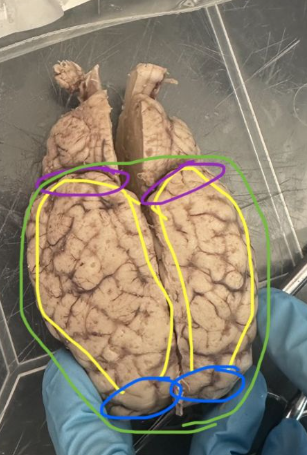

<p>What is the green circle indicating on the sheep's brain?</p>

Olfactory bulb

New cards

What is the yellow circle indicating on the sheep's brain?

Optic nerve/chiasma

74

<p>What is the purple circle indicating on the sheep's brain?</p>

Pons

Cerebrum

What is the blue circle indicating on the sheep's brain?

Frontal lobes

80

Occipital Lobes

Parietal lobes